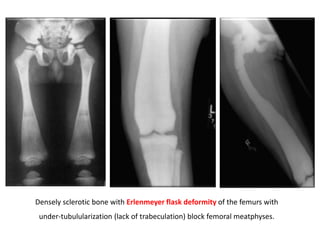

• Erlenmeyer flask deformity = clublike long bones due to

lack of tubulization + flaring of ends

Densely sclerotic bone with Erlenmeyer flask deformity of the femurs with

under-tubulularization (lack of trabeculation) block femoral meatphyses.